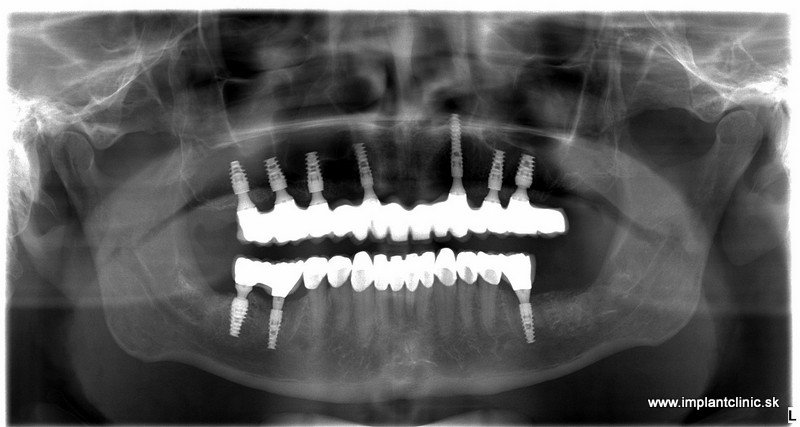

Plán ošetrenia pacienta Jakuba, a teda celková rekonštrukcia jeho chrupu, zahŕňal implantáciu 7 zubných implantátov do hornej čeľuste a 3 zubné implantáty do sánky. V spodnej čeľusti mal pacient na pláne ošetrenia naplánovaných ešte 10 zubných koruniek.

Keďže našou filozofiou je nasadiť fixné provizóriá na implantáty okamžite po implantácii, pacient sa nemusel obávať, že po implantácii odíde z kliniky bez provizórnych koruniek.

Ešte v ten istý deň po implantácii sme pristúpili k výrobe fixných, provizórnych zubných náhrad, ktoré slúžia pacientovi po dobu hojenia implantátov, približne 2 – 3 mesiace.

WeldOne je unikátny koncept používaný pri vyhotovení dočasných náhrad pri ošetrení zubnými implantátmi. Tento koncept umožňuje rýchle a stabilné ošetrenie. Pomocou špeciálnych komponentov je titánový drôt vnútro-ústnym zváraním na pevno prikovaný na implantátové nadstavby. Na titánovú konštrukciu sme pripevnili vopred pripravenú živicovú protézu, ktorú sme upravili podľa potrieb pacienta, zaleštili a priskrutkovali o implantátové nadstavby. Čo poskytuje stabilné a optimálne vystuženie pre dočasné zubné náhrady.

Po upravení a pripevnení provizórnej zubnej náhrady a po artikulácii pacient udával komfortný pocit pri žuvaní a provizórne zubné náhrady boli pre pacienta taktiež veľmi uspokojivé.

Nasledovala ešte kontrola záhryzu niekoľko dní po zákroku a o dva mesiace po implantácii nás pacient navštívil pre kontrolu a odobratie odtlačkov pre výrobu finálnych implantátových koruniek, ktoré sme nasadili pri pacientovej následnej návšteve u nás na klinike.